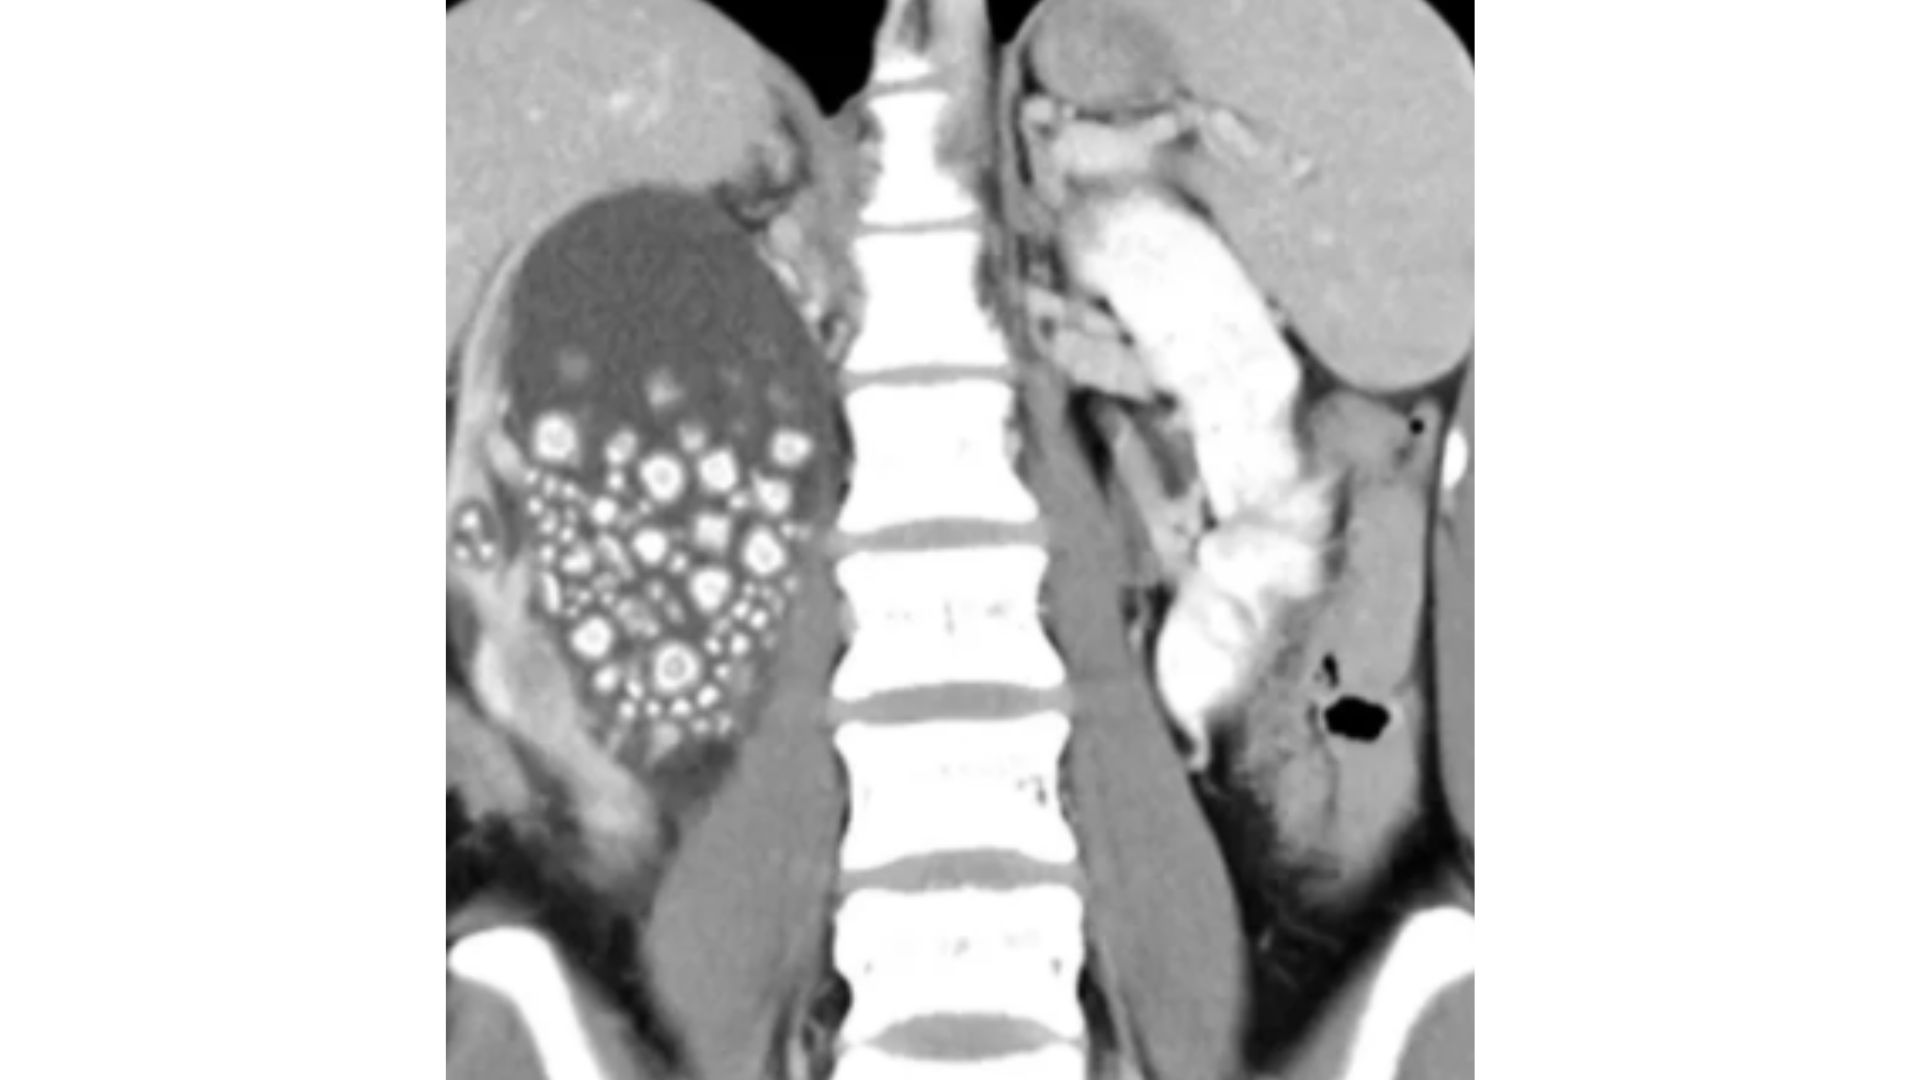

Mesmo com a quantidade assustadora de cálculos renais, a cirurgia foi minimamente invasiva e Yu está com o quadro estável. Nos relatórios, os médicos descreveram que os pedras pareciam “pães cozidos no vapor” e tinham de 0,5 a 2 centímetros de diâmetro.